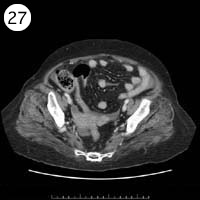

27

57歳 女性